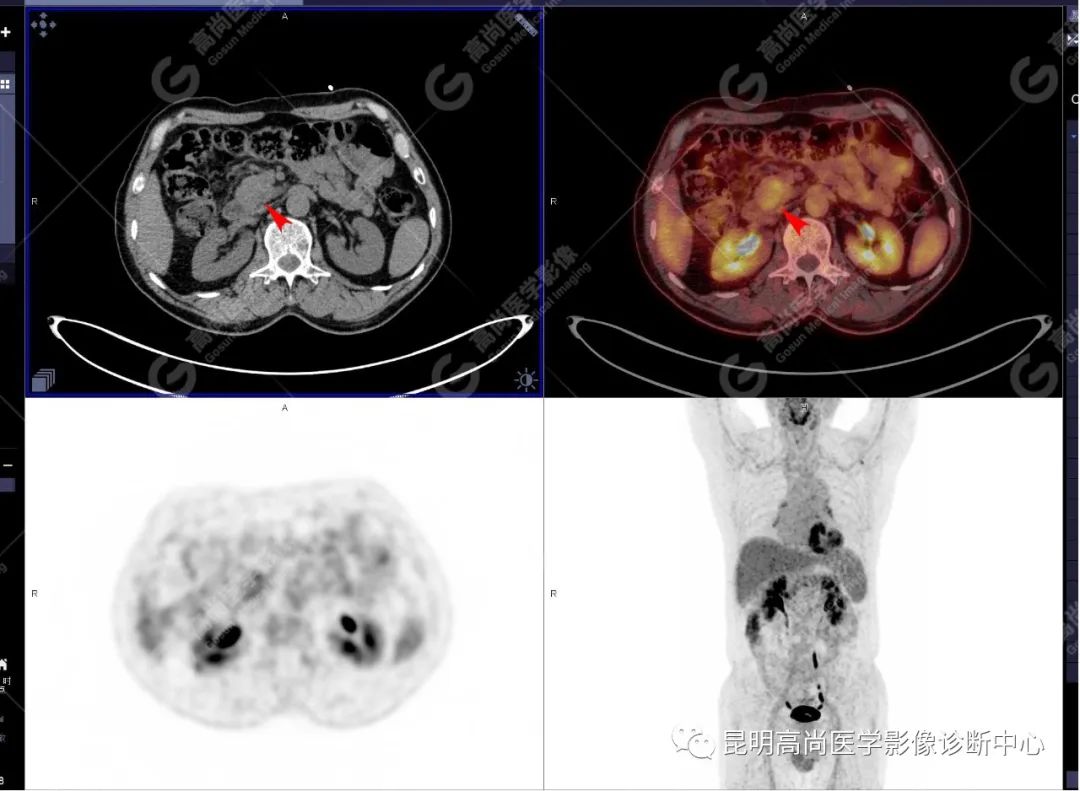

十二指肠壶腹区等密度结节影伴糖代谢持续增高,多考虑恶性病变(壶腹癌),继发主胰管扩张及慢性胰腺炎表现;腹膜后多发淋巴结显示,糖代谢不同程度增高,不除外转移。

(4)18F-FDG PET/CT

在诊断胰腺癌方面具有较高的敏感性,其敏感性可达 85%~90%,特异性可达 55.6%~94%;尤其在鉴别良恶性的囊性肿瘤时,其准确率可达到 94%~95%;PET/CT 是胰腺癌的主要检查手段,它比常规 CT 和 MRI 更具优势,可早期发现远处转移灶;同时可以作为一个独立的、用于预测胰腺癌生存和无进展生存的独立的指标,即 SUV,代谢肿瘤体积,即 MTV。